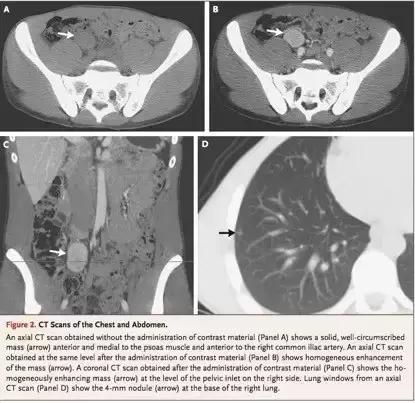

CT可见在右侧骨盆入口平面有一边界清楚的实性腹膜后包块(2.8×3.3×4.6㎝)且有对比增强(Panel B);肺窗下可见一4㎜的结节。